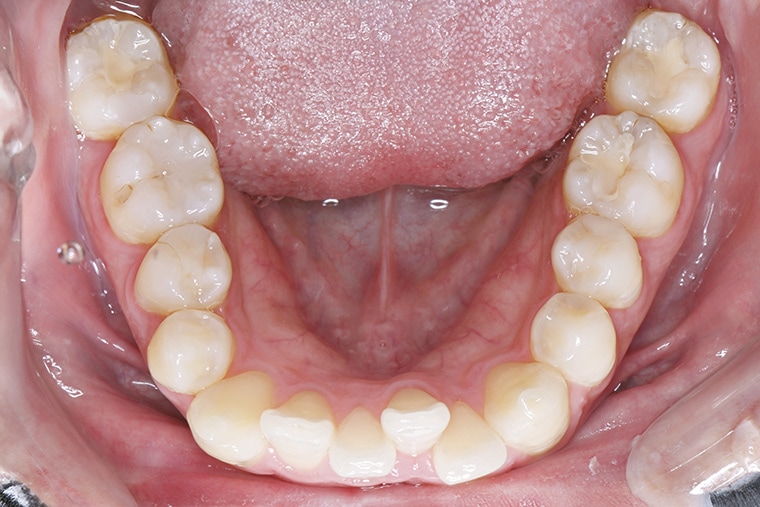

Case Study26歳男性出っ歯のマウスピース矯正-矯正期間8ヶ月(2023年11月開始)